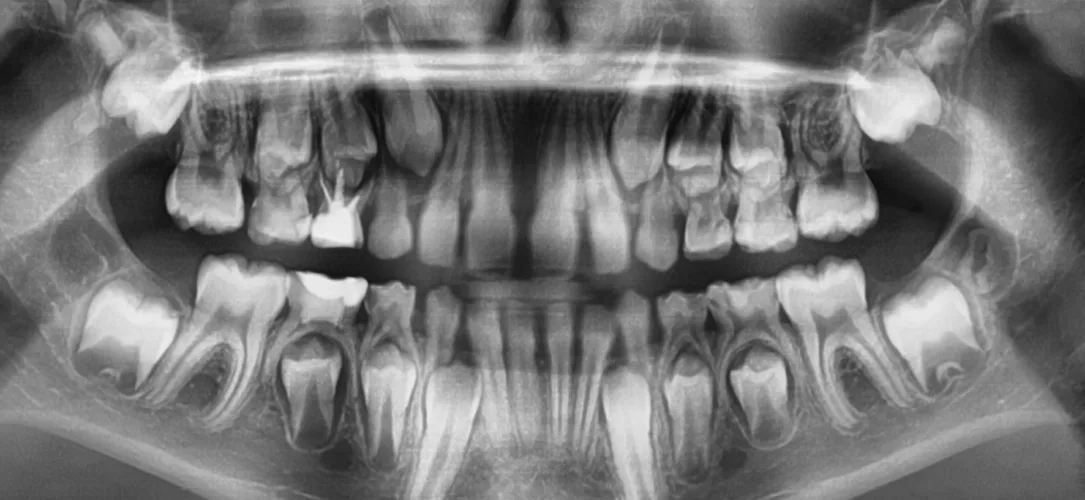

Präeruptive intrakoronale Resorption (PEIR) – mögliche Therapieansätze zu einer seltenen Pathologie

Dentale Entwicklungsstörungen bringen noch große Herausforderungen in die tägliche Routine der Kinderzahnbehandlung. Im Gegensatz zur Molaren-Inzisiven-Hypomineralisation (MIH), die inzwischen als Erkrankung in den zahnärztlichen Praxen wahrgenommen wird, zählt die präeruptive intrakoronale Resorption (PEIR) zu den wenigen bislang kaum bekannten Krankheitsbildern. Beide Erkrankungen sind charakterisiert durch ihre unklare Genese und die hohe Wahrscheinlichkeit einer später erforderlichen endodontologischen Therapie aufgrund einer hohen Kariesprogredienz. Der vorliegende Beitrag fasst das Wichtigste zum Krankheitsbild der präeruptiven intrakoronalen Resorption zusammen und zeigt anhand von 6 Patientenfällen mögliche Behandlungsoptionen auf.